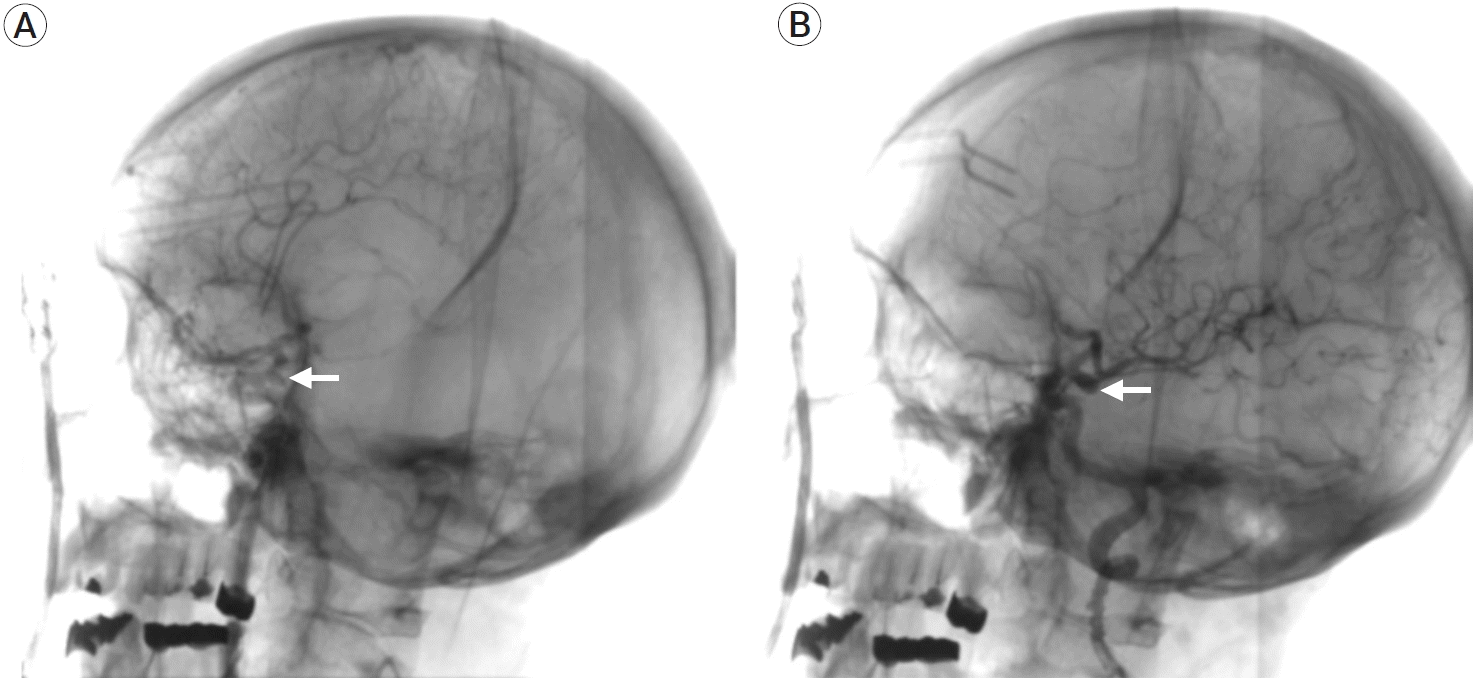

During subarachnoid dissection, a post-fixed optic chiasm with a wide interoptic space was identified (Fig. 2), which allowed a complete dissection of the arachnoid planes, with complete visualization of the contralateral aneurysm’s neck and collateral arteries of the contralateral ICA (pComm and anterior choroidal artery) (Fig. 3). After thorough, the ipsilateral aneurysm was clipped with no difficulty, assessing patency of the ICA branches (Fig. 4) with DSA (Fig. 5). Both aneurysms were permanently clipped with a 7 mm straight clip. The patient’s postoperative course was uneventful, with a sequel left oculomotor palsy.

In our case, we can observe how the unilateral approach can be implemented in selected cases of bilateral pComm aneurysms because the wide interoptic space allows us to visualize the neck of the contralateral aneurysm achieving a correct clipping. Some anatomical factors that allow complete visualization of the contralateral neck are a wide interoptic space and a post-fixed chiasm. However, it should be mentioned that only during surgery can we judge whether these anatomical factors and cerebral edema can provide enough space to maneuver on the contralateral side and perform the clipping. Future studies should be performed using preoperative magnetic resonance image measurements to determine whether we can use the unilateral approach routinely.

Fig. 2.

Artist drawing illustrating the post-fixed optic chiasm and a wide interoptic space, allowing a complete view of the neck of the contralateral pComm aneurysm. pComm, posterior communicating